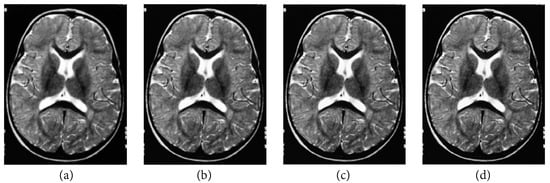

The following numerical results are proposed: Figure 2 presents the original grayscale images for (a) X-ray film of the brain and (b) X-ray film of the right shoulder. Figure 3 and Figure 6 are blurred X-ray films of the brain and the right shoulder images with filtering M i x in the part of degradation of Figure 1. In this example, we set N = 4 . So, we have M 1 x , M 2 x , M 3 x , and M 4 x . Figure 4a, X-ray films of the brain and the right shoulder images were obtained via Theorem 2. Figure 4b, X-ray films of the brain and the right shoulder images were obtained via Theorem 3.1 in [16] (Khuangsatung and Kangtunyakarn’s method). Figure 9 is an X-ray film of the brain image that was recovered via the proposed method that was tuned for the parameter λ.

Figure 3. Blurred X-ray film of the brain image with filtering M i x by (a) M 1 x , (b) M 2 x , (c) M 3 x and (d) M 4 x .